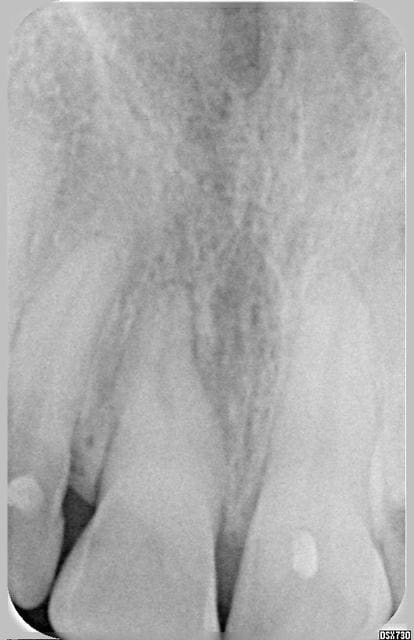

Patiente, 23 ans, Choc sur la centrale quelques années auparavant, tests de vitalité négatifs depuis des années, changement teinte suite certainement à une nécrose pulpaire.

La dévitaslisation était prévue par mon prédecesseur quelques années auparavant mais la patiente n'a pas donné suite aux rendez-vous.

Elle revient vers moi pour des motifs esthétiques (éclaircissement)

Voici les 3 radios pré-op, depuis 04, jusqu'au 05.11.07

18.06 - Eugenol

19.07 - Eugenol

05.11 - Eugenol